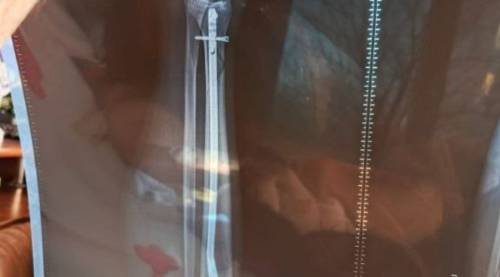

В апреле 2025 года на берегу озера в поселке Трудовом пьяная компания избила мужчину, сломав ему ногу в двух местах. Пострадавший перенёс две операции.

Уточняется, что 2 апреля 2025 года в дежурную часть отдела полиции Советского района г. Владивостока поступила телефонограмма из медицинского учреждения о том, что в больницу обратился 42-летний мужчина с переломом ноги.

Согласно заключению судебно-медицинской экспертизы владивостокцу причинен тяжкий вред здоровью. На основании чего возбуждено уголовное дело по части 1 статьи 111 УК РФ.